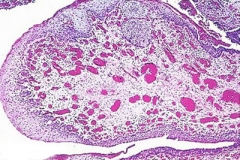

膀胱炎诱因有结石、异物、肿瘤或阻塞性病变,包括由于神经系统疾产生的排尿功能障碍等。膀胱炎的急性炎症的病理变化有粘膜充血、水肿、出血和溃疡形成,并有脓液或坏死组织。慢性炎症主要有粘膜增生或萎缩、肉芽组织形成,并有纤维组织增生,膀胱容量减少;或并发阻塞所引起的肌肉肥大,膀胱容量增大甚至有憩室形成等改变。还有一种特殊的炎症变化是坏疽性膀胱炎,为梭形杆菌、产气荚膜杆菌等引起的严重膀胱炎症。

腺性膀胱炎的诊断主要是依据病理学,也就是在经尿道的膀胱镜下取病理活检,若是有滤泡样增生或水草样簇样增生,就提示是腺性膀胱炎。由于本病有恶变成腺癌或膀胱癌的可能,...